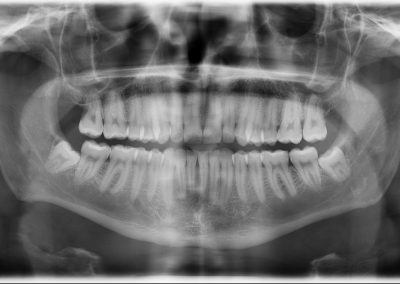

Radiologia. Las radiografías dentales son un tipo de imagen de la cavidad oral, en la que podemos ver todas las estructuras que la componen.

Las intraorales son las radiografías de un conjunto de dientes o un diente en concreto, mientras que las extraorales son la Ortopantomografía muy utilizada para diferentes diagnósticos y la Teleradiografía Lateral de Cráneo para estudios de ortodoncia.

En la ortopantomografía o panorámica vemos todas las estructuras de la cavidad oral